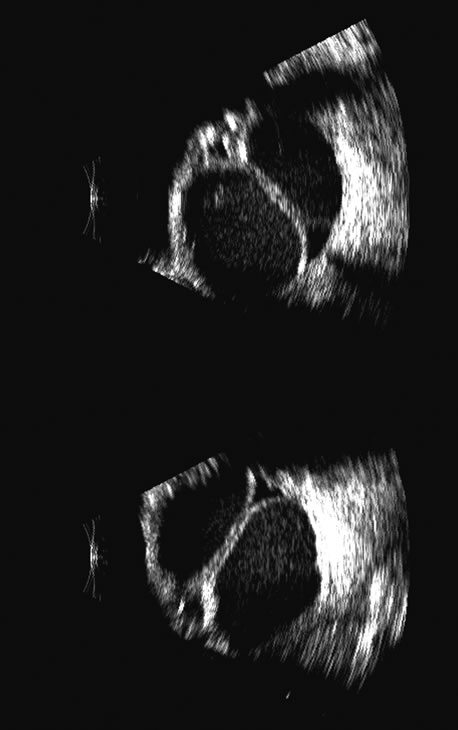

Hypotony is easily diagnosed by direct measurement of intraocular pressure, but the underlying cause is difficult to evaluate.11 High-frequency ultrasound scans can easily reveal separation of the ciliary body and the sclera. This allows different forms of hypotony to be determined—for example: tractional with membrane attached; primary as idiopathic, often inflammatory or hemorrhagic; and dehiscence secondary to iridodialysis or scleral perforation (Fig. 6).

Fig. 6. Hypotony of the eye generally is easily diagnosed by a separation of the ciliary body from the sclera. We have noted several types of such separation, such as tractional, primary (idiopathic), and dehiscence secondary to iridodialysis or scleral perforation, as in filtration procedures. In our series, greater than two clock hours of separation is typical of hypotony. The lower figure shows a concomitant thickening of the retina-choroid complex, also seen in hypotony (arrows). Long-standing hypotony typically has a shortened globe and possible retinal or choroidal separation.